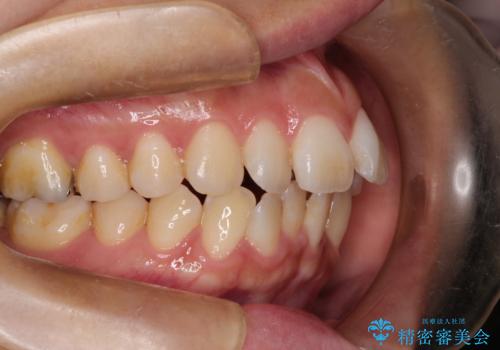

下顎の正中を上顎に合わせる処置が難航し、期間が長引きました。

最終的には上下の正中も合い、横顔の印象が変わるほどスッキリとした口元となりました。